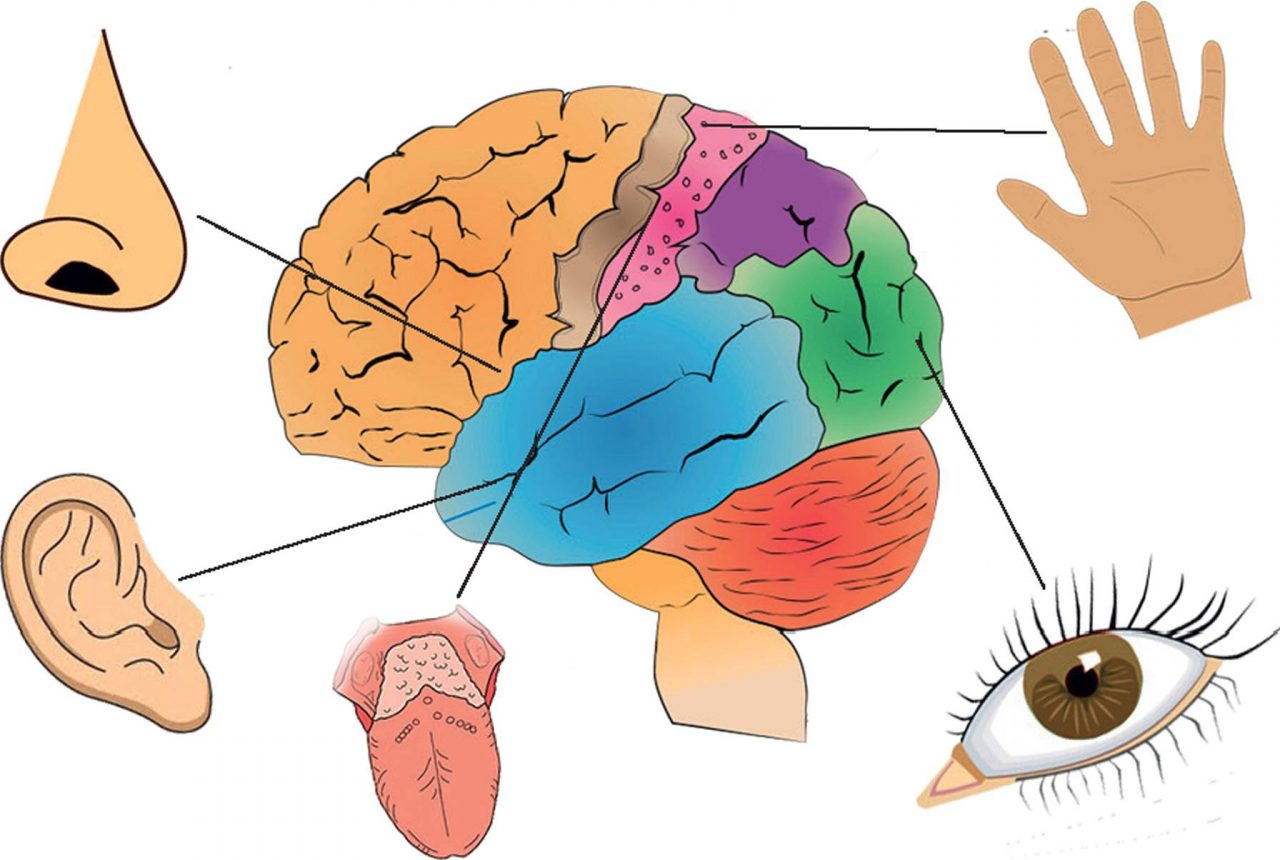

Физиология памяти: Механизмы и исследования